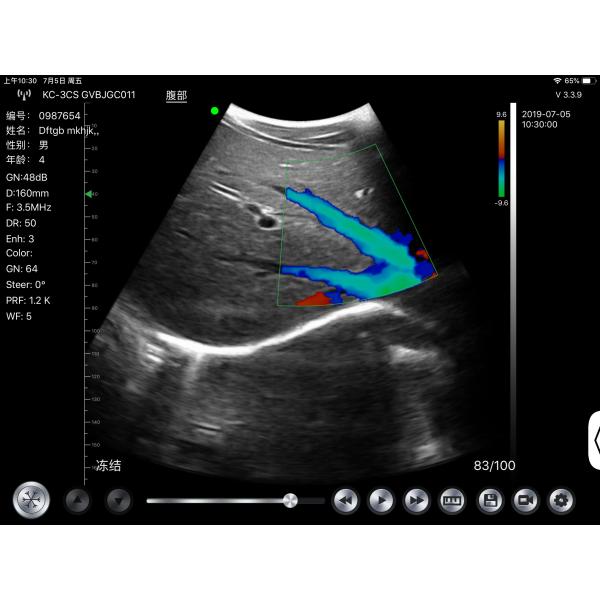

Type : Doppler Ultrasound Equipment,Portable Ultrasonic Diagnostic Devices,Veterinary Ultrasound Scanner

Imaging mode : B+B,B+M,M

Name : Cardiac portable ultrasound machine price,Cardiac Portable Color Doppler Ultrasound,Cheap Ultrasound Machine,Wireless Color doppler Ultrasound Probe

Product name : Full Digital Color Doppler Diagnostic System,medical ultrasound,Transvaginal ultrasound scanner,Cheap B/W ultrasound machine with trolley

Item : Color Doppler System,ultrasound baby scan machine,Doppler portable ultrasound machine

Display mode : B,B+B,M,B+M

GEN4proCT is Wireless Wifi dolppers Convex Array Probe Type Ultrasound Scanner. This wireless Wifi Convex Array Probe with integrated ultrasound circuit boards inside,then realize the functions of a ultrasound scanner(ecografos). It can be uesed at many occasions such as In emergency clinical, hospital ward inspection. In addition, CT is easy to poerate because it has unique design with three buttons which is an ecografo portail or portable ultrasound machine.

G10cx G10ct Portable Ultrasound Scan Machine Transducer Wireless Doppler Ultrasound Probe Images |